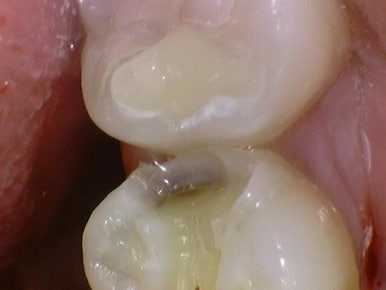

필요한 경우에는 치료 중간중간 바로바로 구강카메라로 찍어서

깊은 충치를 보여드립니다.

충치치료, 레진, 크라운, 인레이, 발치 등 왜 그 치료를 해야하는지

과잉진료없이 객관적인 근거를 보여드립니다.

치료 전, 치료 중간 신경치료해야 할 만큼 깊은 충치를 보여드리기 위해 찍은 사진